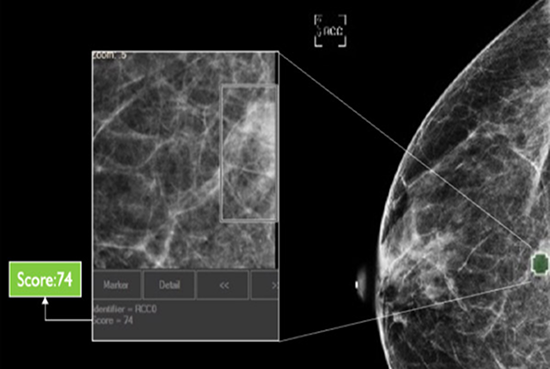

Automatic Reading Drawing Attention on Regions of Interest

cmAssist has the ability to quickly detect key regions of interest on a mammogram, and accurately quantify and label anomalies as suspicious or, instead, verifiably benign. cmAssist does this by searching all the views of a digital 2D-mammogram for abnormal areas of density, mass or calcification and by highlighting suspicious areas requiring further analysis. Once anomalies are flagged in the system, cmAssist then marks the mammogram and highlights the identified anomalies.

Which Patient to Spend More Time on?

The software also generates a unique, data-driven neuScore™ that provides radiologists with a quantitative measure of suspiciousness in a marked region of interest, ranging from 0 (least suspicious) to 100 (highly suspicious). This score can be tracked over time to evaluate the stability or evolution of identified anomalies.